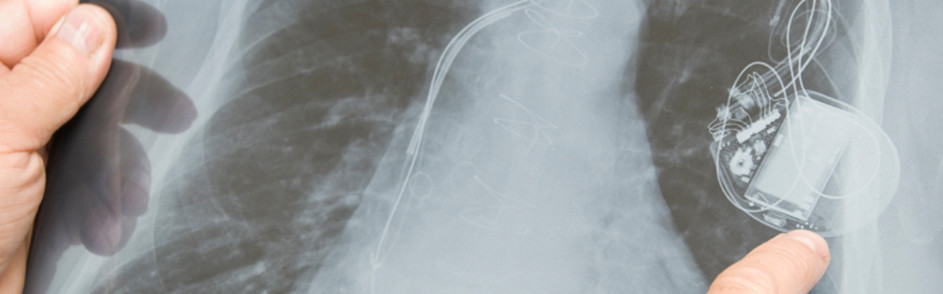

An implantable cardiac defibrillator, often called an ICD, is a small electronic device installed inside your chest to prevent sudden death from cardiac arrest due to abnormally fast or erratic heart rhythms (tachycardia or ventricular fibrillation, respectively).

The ICD monitors your heart rhythm. When your heart is beating normally, the device is inactive. If your heart develops a life-threatening tachycardia, the ICD delivers an electrical shock or shocks to the heart to return the heart rhythm to normal.

Pacemakers may be permanent or temporary. A permanent pacemaker is implanted into your chest during a minor surgical procedure. A short stay in the hospital may be required, and you may need to take medications afterward to help your heart maintain a normal rhythm.

For pacemaker and ICD implantations, a small incision is made in the shoulder area where the device is placed. You will be monitored throughout the procedure to ensure your comfort and safety. You may need to stay in the hospital for a short period of time for observation. Your doctor will also provide instructions on wound care, activity restrictions and follow-up visits.